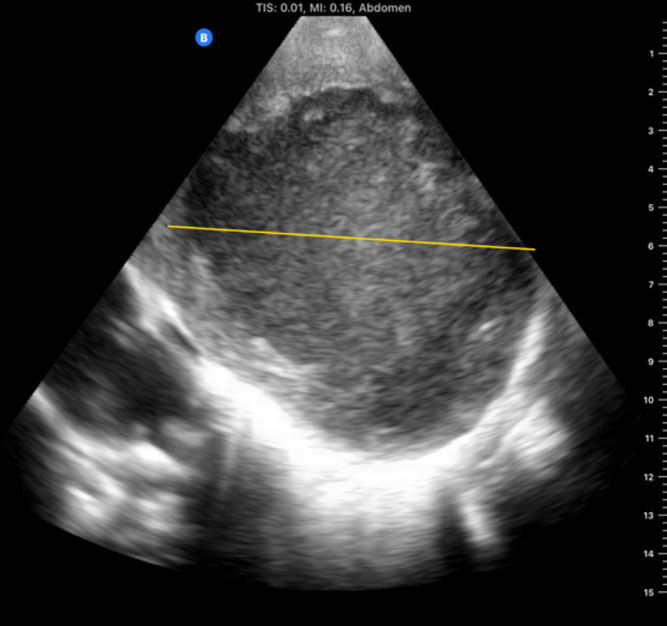

First-hand experience of recent expeditions to low-resource countries (eg, Chad and Sudan), as well as conflict zones such as the Ukrainian front lines following the Russian invasion on February 2022, reveals the substantial clinical utility that PoCUS may have, particularly when other imaging modalities are unavailable. During a recent expedition to Chad, a portable handheld ultrasound device directly assisted in making critical diagnoses and performing life-saving interventions in several men, women, and children. In total, 12 patients (mean age 14.9 years) were managed with the aid of PoCUS with the most common scenarios being trauma after motor vehicle accidents, respiratory failure, and obstetric complications. The most frequent study types performed were the Extended Focused Assessment with Sonography in Trauma (eFAST), cardiac, and lung studies. Within this group of patients, 2 died within this period (a 13-year-old girl with intra-abdominal perforation who traveled for 5 days to the hospital and a 12-year-old extremely malnourished girl who arrived in severe shock and required immediate CPR), and 2 remained with unknown outcomes but carried grave prognoses. PoCUS directed management in 75% of patients, including pulmonary edema in a laboring woman, an amoebic liver abscess diagnosis and ultrasound-guided drainage in a 3-year-old girl, a diagnosis of large pericardial effusion in a 10-month-old boy with Trisomy 21, and the diagnosis of intracranial hypertension using ocular ultrasound in an unconscious 13-year-old involved in a car accident as a pedestrian, suggesting intracranial bleeding.